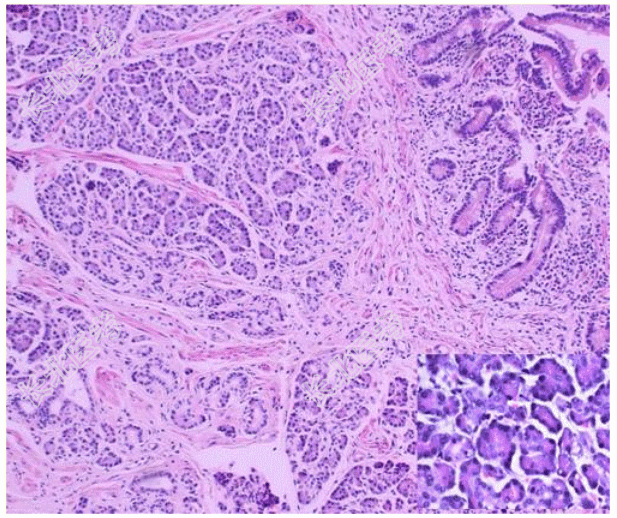

- [材料题] 患者女,35岁,十二指肠乳头下方3 cm处发现一个直径约1.5 cm肿块,呈息肉状生长。切面见肿块淡黄色,位于黏膜下,与周围界限欠清;表面黏膜大多光滑,中央可见浅溃疡形成。光镜下组织形态如图所示。病理诊断为胰腺异位。